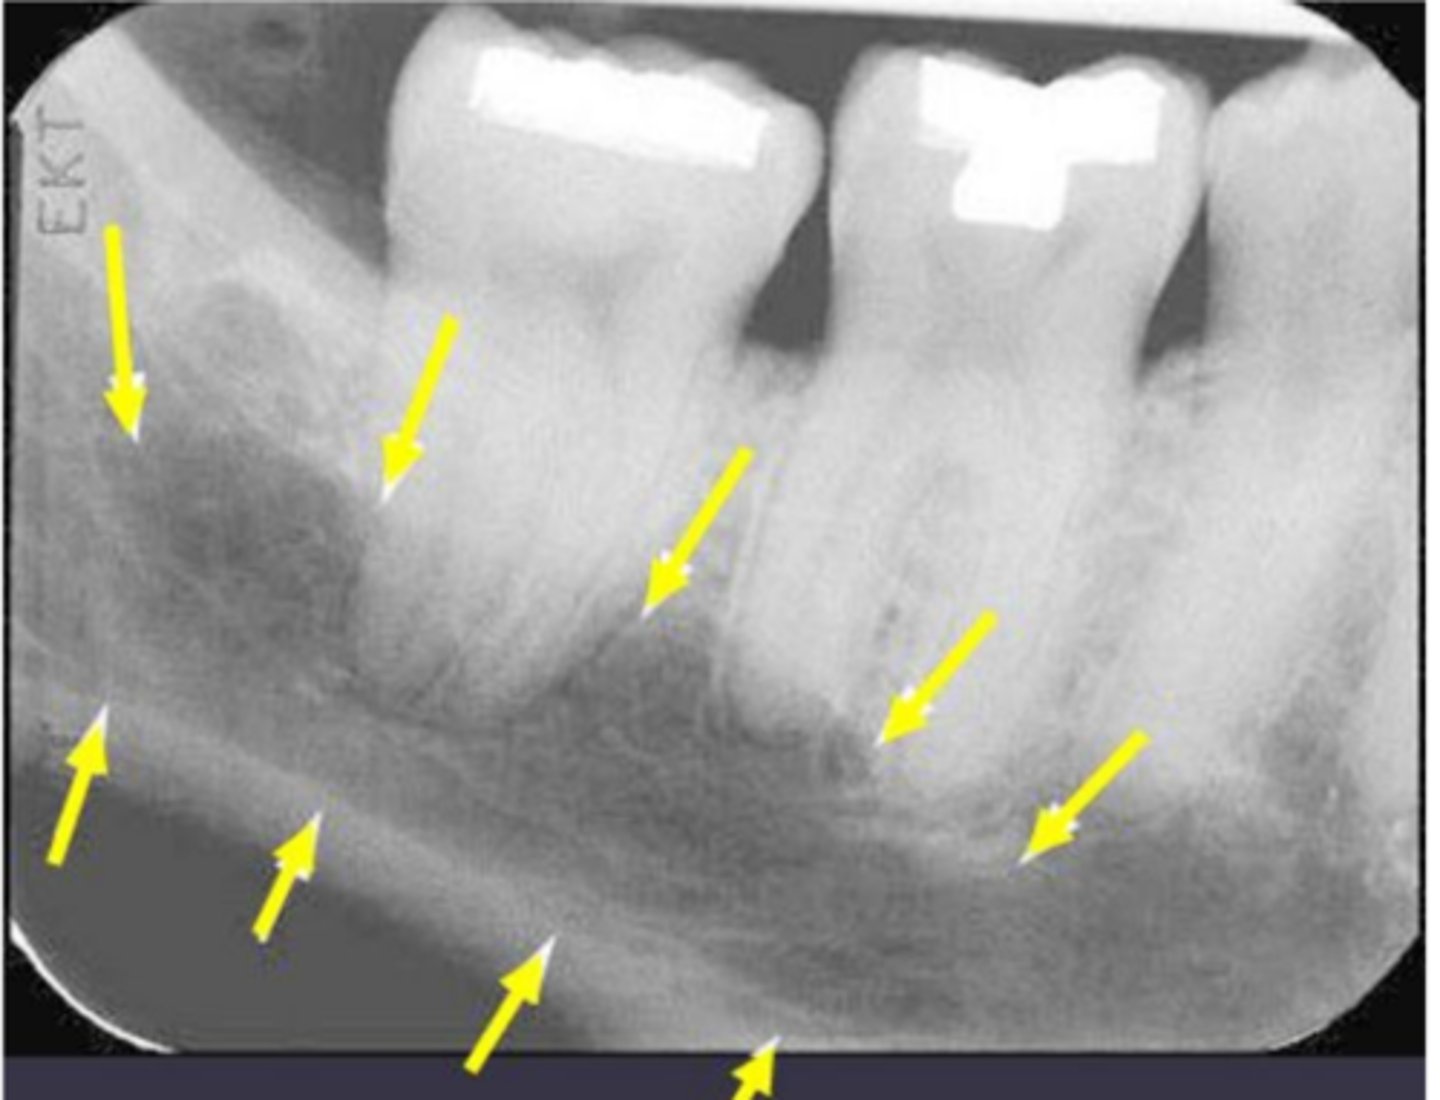

anterior border of the ramus

Name the structure the white arrow is pointing to.

<p>Name the structure the white arrow is pointing to.</p>

internal oblique ridge or mylohyoid ridge

Name structure the black arrow is pointing to.

<p>Name structure the black arrow is pointing to.</p>

Submandibular fossa

Name the radiolucent area indicated by the arrows

<p>Name the radiolucent area indicated by the arrows</p>